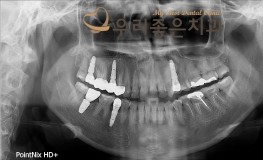

우리좋은치과 치아 상실로 인한 임플란트 보철 치료 (최** 2019.04.09~11..

No.348

임플란트

2019-11-25